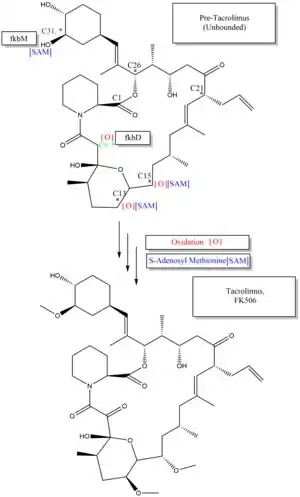

The starter unit, DHCHC from the chorismic acid is formed by fkbO enzyme and loaded onto CoA-ligase domain (CoL). Then, it proceeds to NADPH dependent reduction(ER). Three enzymes, fkbA,B,C enforce processes from the loading module to the module 10, the last step of PKS 1. fkbB enzyme is responsible of allylmalonyl-CoA synthesis or possibly propionylmalonyl-CoA at C21, which it is an unusual step of general PKS 1. As mentioned, if two methoxymalonyl CoA molecules are substituted for two malonyl-CoA molecules, they will take place in module 7 and 8 (C13 and C15), and fkbA enzyme will enforce this process. After the last step (module 10) of PKS 1, one molecule of L-pipecolic acid formed from L-lysine and catalyzed through fkbL enzyme synthesizes with the molecule from the module 10. The process of L-pipecolic acid synthesis is NRPS enforced by fkbP enzyme. After synthesizing the entire subunits, the molecule is cyclized. After the cyclization, the pre-tacrolimus molecule goes through the post-synthase tailoring steps such as oxidation and S-adenosyl methionine. Particularly fkbM enzyme is responsible of alcohol methylation targeting the alcohol of DHCHC starter unit (Carbon number 31 depicted in brown), and fkbD enzyme is responsible of C9 (depicted in green). After these tailoring steps, the tacrolimus molecule becomes biologically active.[53][54][55]